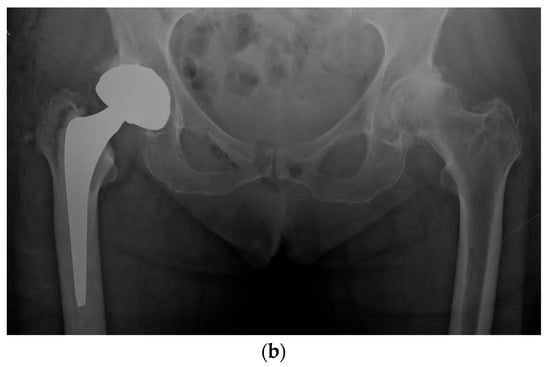

We prefer to use a fixed neck stem with three different neck angle options to better meet the different patients’ anatomies rather than a stem design with a unique angle and two different offsets (standard/lateralized). Less influenced by the risk of instability, surgeons using LDH THA can better optimize a patient’s leg length and femoral offset (Figure 5). In our experience and the literature, up to 10 mm of leg length difference can be tolerated; a shorter leg is much better tolerated than a longer one by patients []. In the cases where we hesitate between a shorter or a longer head (example: 0 mm vs. a +4 mm), we, therefore, select the shorter one.

Figure 5.

(a) Antero-posterior pelvis radiograph of a 55-year-old man with a right metal-on-metal 28 mm THA and severe osteoarthritis of the left hip. (b) Postoperative radiograph after a left LDH THA with leg length and femoral offset restoration.